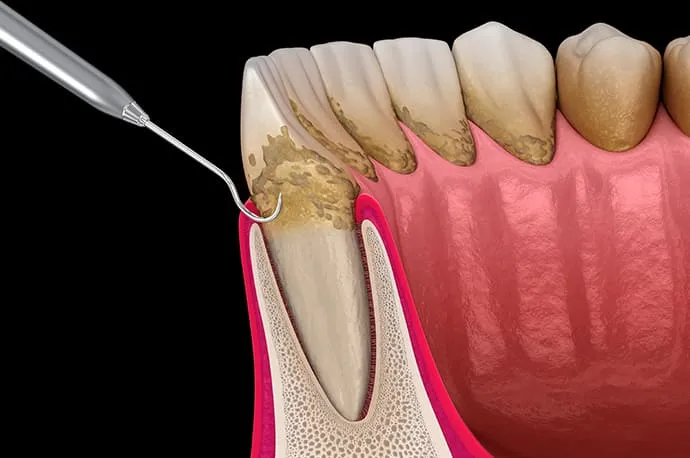

歯周基本治療では、歯ぐきの隙間から器具を入れ、歯ぐきの下に付着した歯石を除去します。この際、手の感覚を頼りに処置を行うため、平たい歯石や器具が入りにくい部位では、歯石が取り残されてしまうことがあります。

歯石の取り残しがある場合や、歯周組織の改善が十分に認められない場合には、歯ぐきを切開して開き、歯石を直接目で確認しながら除去します。

従来は、汚染源を取り除くことが治療の中心でしたが、近年では歯周組織の再生を目的とした術式や材料も登場しています。当院では、歯周組織再生療法に高い専門性を持つドクターが在籍し、状態に応じた治療を行っています。